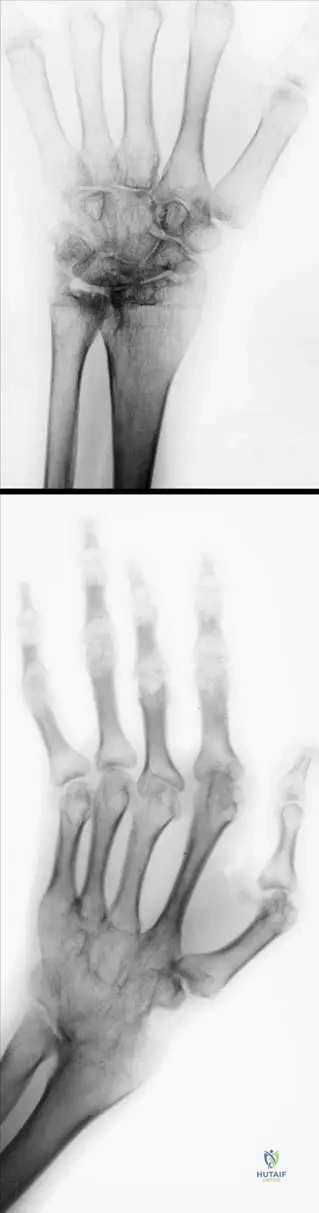

Question 74

A 38-year-old female presents with early symptoms of rheumatoid arthritis. Radiographs of her hands are obtained to assess for initial changes. What is a typical early radiographic finding in rheumatoid arthritis?

View Answer & Explanation

Correct Answer: C

Rationale: Early radiographic changes in rheumatoid arthritis typically include soft tissue swelling, juxta-articular osteopenia (often described as striped periarticular atrophy or osteoporosis), and marginal erosions. Diffuse osteosclerosis, joint space widening, large subchondral cysts, and carpal ankylosis are not characteristic early findings; ankylosis is a late-stage change. The main distractor, A, is incorrect as osteosclerosis is not an early feature of RA; rather, osteopenia is seen.